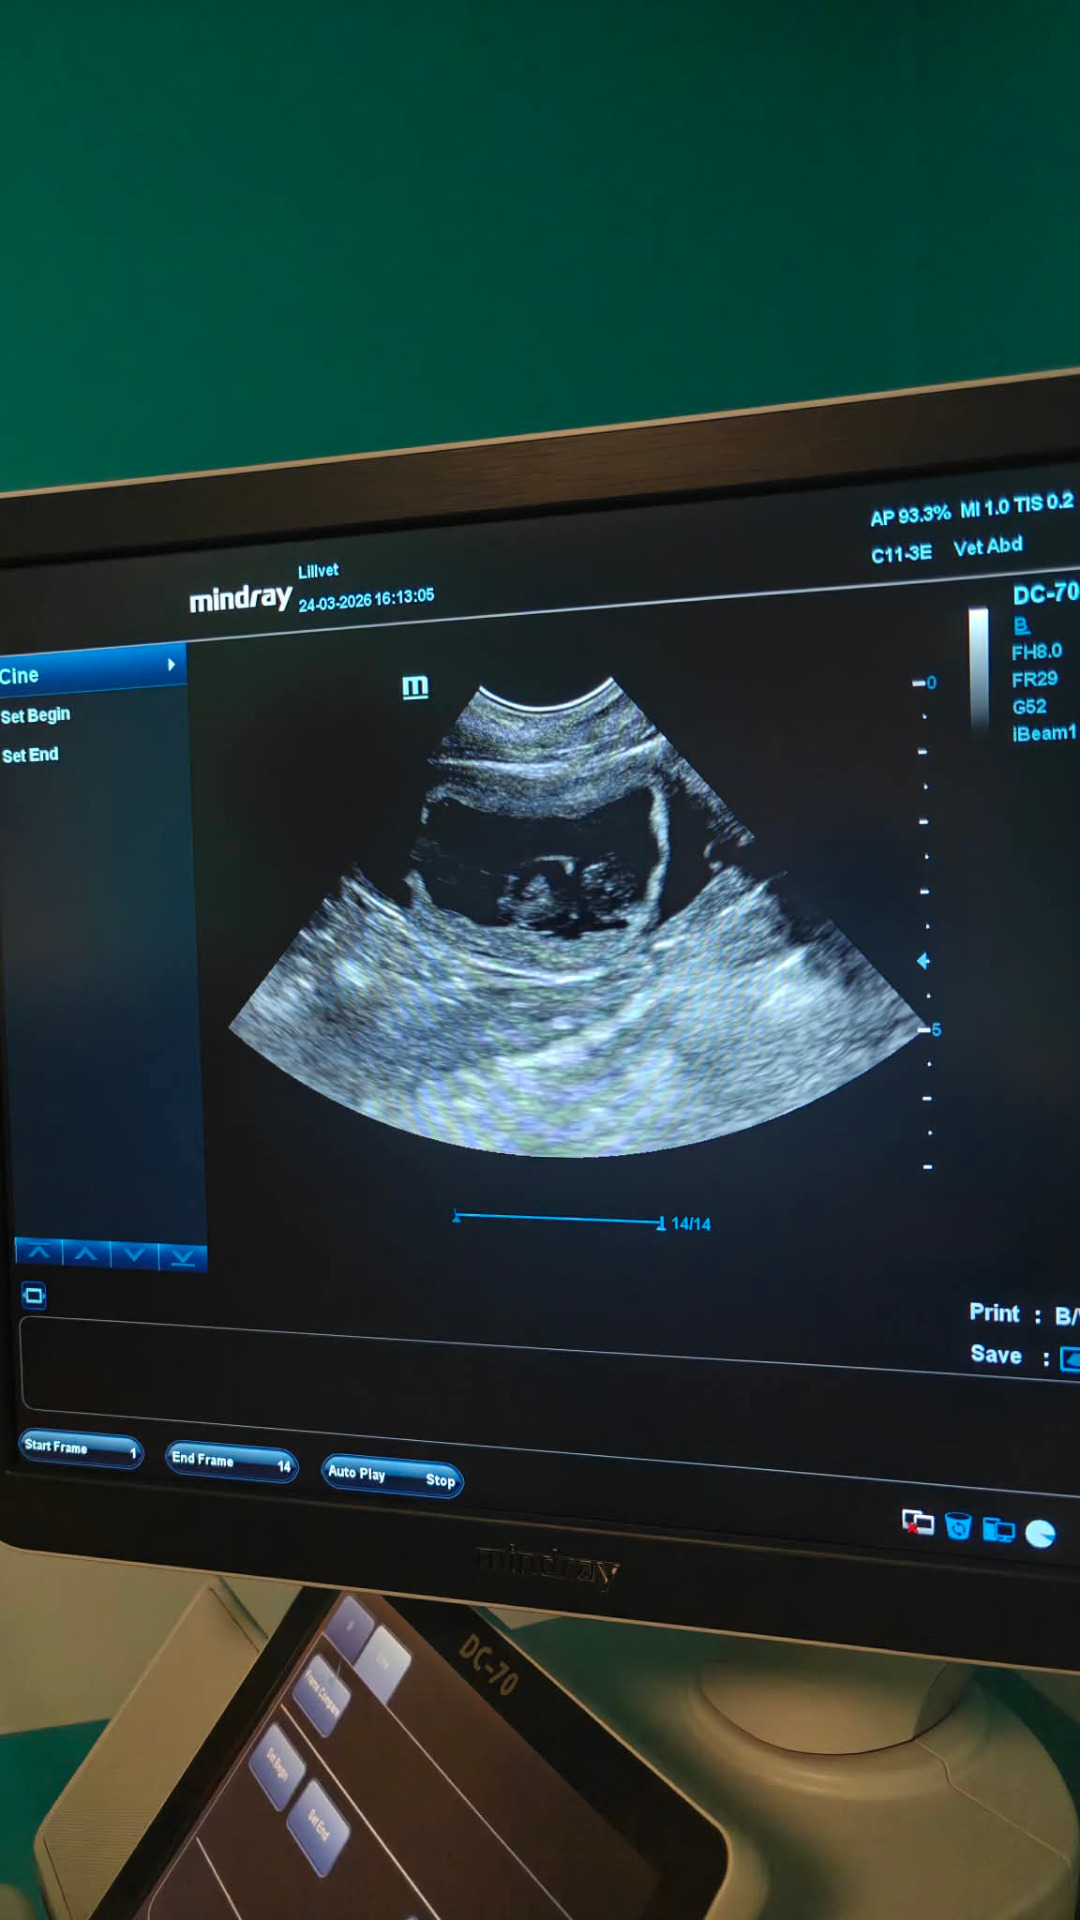

Kun ultralaite asetettiin mahan päälle, sieltä pompsahti jo heti ensimmäinen sankari kuviin!

Näytöltä tarkastettiin koko masun tilanne, kaikilla näkyi sykkivät sydämet ja selkärankakin jo erottui. Laskelmien mukaan siellä olisi arviolta 7 pentua mutta me käymme röntgenissä vielä tiineyden loppuvaiheilla varmistamassa tämän.